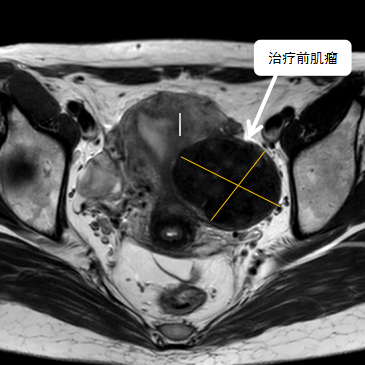

術(shù)前影像資料

經(jīng)過兩個月的藥物預(yù)處理,完善術(shù)前準(zhǔn)備,治療當(dāng)天陳主任帶領(lǐng)團(tuán)隊在3.0T磁共振清晰圖像引導(dǎo)下對子宮肌瘤進(jìn)行精準(zhǔn)消融,患者全程清醒,沒有明顯疼痛,經(jīng)過1個多小時的精細(xì)操作,手術(shù)非常成功,消融率接近90%,內(nèi)膜未見損傷!觀察一個小時后患者即自行回家。

術(shù)后即刻行增強磁共振檢查,顯示病變被消融近90%,內(nèi)膜未見損傷